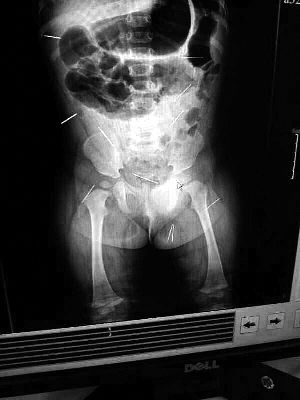

山東聊城11個月女嬰萱萱(化名)疑似被人以12根鋼針插滿臀部、腹腔等部位,昨天在兒童醫(yī)院會診后,醫(yī)生稱3根針靠近胸腔最危險,首批先行取出,預(yù)計(jì)將在下周二手術(shù)。孩子父母稱孩子一直由家人照顧,自家與他人并無冤怨。山東警方表示正在偵破中,不便透露案情。

“要不是當(dāng)初那幾個紅點(diǎn),可能到現(xiàn)在我們還不知道孩子身體里有鋼針!”昨天,在兒童醫(yī)院住院處,萱萱爸爸范先生稱,日前原本很愛笑的萱萱突然變得有些焦躁,一抱起來就哭,孩子母親偶然間在萱萱屁股上發(fā)現(xiàn)了幾個小紅點(diǎn)兒,原以為是蚊蟲叮咬,就醫(yī)結(jié)果卻讓人不寒而栗。“醫(yī)院拍出的片子上,萱萱的體內(nèi)有12根鋼針,插滿臀部、腹腔、骨盆等各個部位。”范先生介紹,因?yàn)殇撫樢焉钊塍w內(nèi),要是孩子不哭鬧,他們很難發(fā)現(xiàn)。

北京晨報記者了解到,目前體內(nèi)的12根鋼針多分布在孩子的臀部,一根在腹部,其余3根在胸腔附近,其中一根很接近心臟?!耙?yàn)楹⒆犹?,醫(yī)生們害怕取針的時候?qū)λ斐蓚?,在胸腔附近?針可能會威脅她的生命”。

截至昨晚6時許,北京晨報記者從兒童醫(yī)院宣傳部門了解到,孩子目前已經(jīng)接受完專家會診,暫定今天和下周一進(jìn)行術(shù)前檢查,如果一切順利將在下周二手術(shù),“孩子暫時沒有生命危險”。